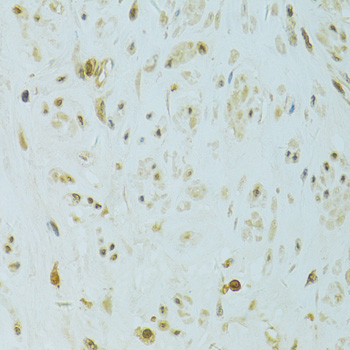

Immunohistochemistry of paraffin-embedded human uterus using XBP1 at dilution of 1:100 (40x lens).

,

Immunohistochemistry of paraffin-embedded human uterine cancer using XBP1 at dilution of 1:100 (40x lens).